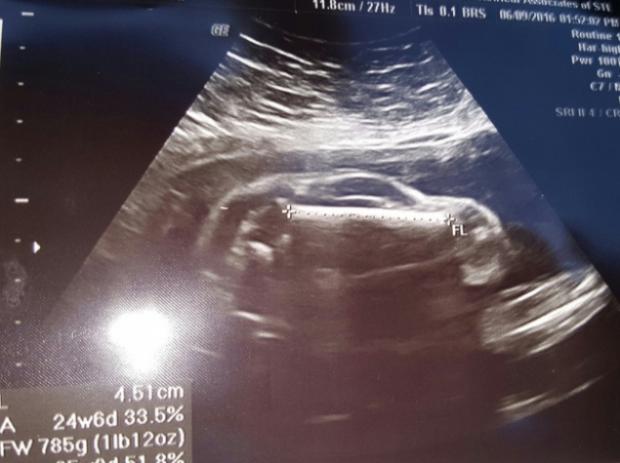

O femeie a reusit sa socheze o lume intreaga cu ecografia ei.

Dupa ce a fost supusa unei radiografii, medicii au facut o descoperire aproape inexplicabila. In pantecele femeii se afla un corp strain si care nu parea sa prevesteasca o sarcina.

Potrivit Metro.co.uk, femeia din Marea Britanie a reusit sa treaca de la agonie, la extaz, in urma ecografiei. Initial, medicii nu au putut sa-si dea seama daca femeia este insarcinata sau nu si asta pentru "fetusul" semana mai degraba cu o...masina.

La o analiza mai minutioasa, ginecologul a felicitat-o pe viitoarea mamica si i-a spus ca este insarcinata in 24 de saptamani.

Taticul, in schimb, a facut haz de necaz de intreaga situatie si a publicat ecografia pe internet, acolo unde a devenit virala. Mai multi utilizatori s-au amuzat de patania cuplului, iar glumele pe tema automobilelor au curs imediat.